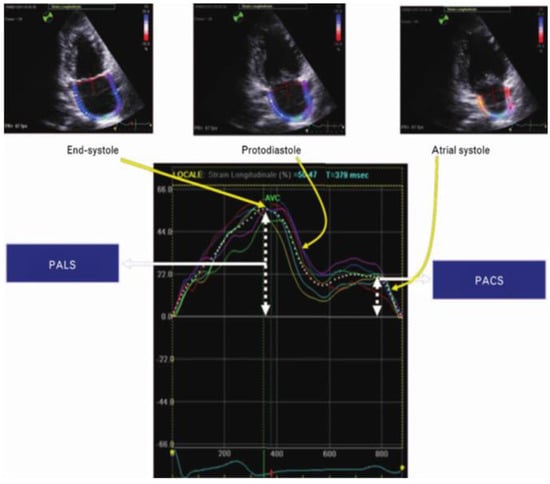

- Peak atrial longitudinal strain (PALS), measured at the end of the atrial reservoir phase. Which in normal subjects is greater than 40%. In patients with atrial fibrillation it has been seen that the reduction in strain reflects structural alterations of the left atrium (wall fibrosis) [36] (Figure 2)

- Peak atrial contraction strain (PACS) identified just before the onset of the active phase of atrial contraction [37], which indicates the contribution of the active contraction of the left atrium to the filling phase of the left ventricle [38] and which is lacking in patients with permanent atrial fibrillation.